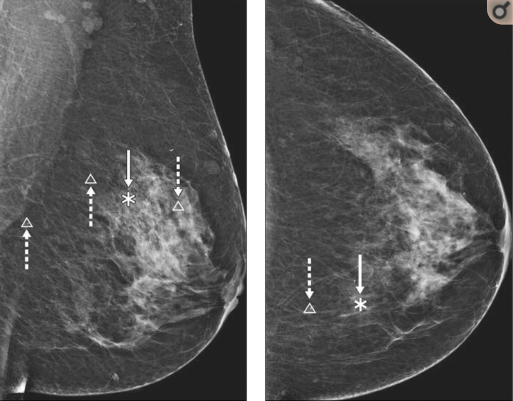

В ряде зарубежных научных публикаций было продемонстрировано, что алгоритм искусственного интеллекта для выявления рака молочной железы по изображениям маммограммы так же эффективен, как и работа высококвалифицированных врачей-рентгенологов.

В частности, при поддержке Императорского центра биомедицинских исследований NIHR ученые разработали и обучили алгоритм искусственного интеллекта с использованием маммографических изображений почти 29 000 женщин в Великобритании и США.

Затем эту систему использовали для выявления наличия рака молочной железы на маммограммах женщин, о которых было известно, что у них онкологии не было, либо наоборот — они имели подтвержденный биопсией рак молочной железы.

Результаты, опубликованные в журнале Nature, поподтвердили, что алгоритм искусственного интеллекта превзошел по точности как архивные диагнозы, так и заключения шести опытных радиологов, которые интерпретировали 500 случайно выбранных случаев.

Алгоритм согласно результатам эксперимента также уменьшил долю ошибок скрининга там, где рак был либо неправильно идентифицирован, либо где он мог быть пропущен.

Международная группа экспертов, в которую входят исследователи из Google Health, Imperial College London, DeepMind, NHS и Северо-западного университета в США, пришли к выводу, что ИИ, прошедший соответствующее обучение, может поддерживать принятие клинических решений в будущем.